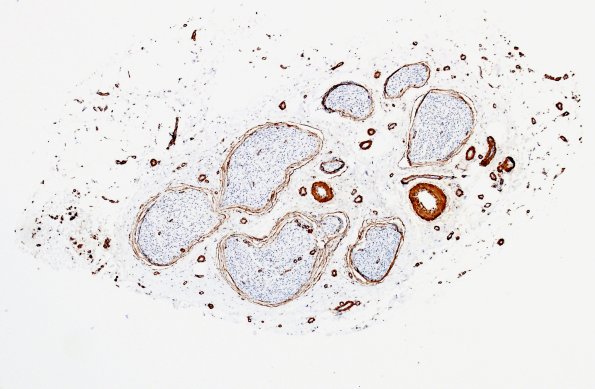

Washington University Experience | PERIPHERAL NEUROPATHY | 11 VASCULITIS - VASCULOPATHY | 1 Normal Vasculature | 4A3 Nerve, vasculature (Case 4) SMA 2

4A3,4 Several magnifications of an epineurial arteriole and several venules contrast with the relative hypovascularity of the endoneurium. (SMA IHC)